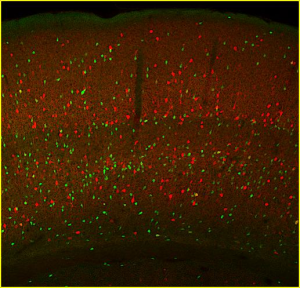

Δεναξά Μυρτώ, Επιστημονικός Υπεύθυνος του ερευνητικού έργου με τίτλο: «Πώς καθορίζονται τα λειτουργικά χαρακτηριστικά συγκεκριμένων ομάδων νευρικών κυττάρων του εγκεφάλου, που ονομάζονται ενδονευρώνες»

Η ισορροπία μεταξύ διέγερσης και κατάστολής είναι θεμελιώδης για τη βέλτιστη λειτουργία του εγκεφάλου. Οι ενδονευρώνες αποτελούν την κύρια πηγή αναστολής των διεγερτικών νευρικών κυττάρων του εγκεφαλικού φλοιού. Αλλαγές στον αριθμό ή την λειτουργία τους έχουν συσχετισθεί με ποικίλες νευροαναπτυξιακές και νευροψυχιατρικές διαταραχές, όπως επιληψία, σχιζοφρένεια και διαταραχές του φάσματος του αυτισμού.

Η ισορροπία μεταξύ διέγερσης και κατάστολής είναι θεμελιώδης για τη βέλτιστη λειτουργία του εγκεφάλου. Οι ενδονευρώνες αποτελούν την κύρια πηγή αναστολής των διεγερτικών νευρικών κυττάρων του εγκεφαλικού φλοιού. Αλλαγές στον αριθμό ή την λειτουργία τους έχουν συσχετισθεί με ποικίλες νευροαναπτυξιακές και νευροψυχιατρικές διαταραχές, όπως επιληψία, σχιζοφρένεια και διαταραχές του φάσματος του αυτισμού.